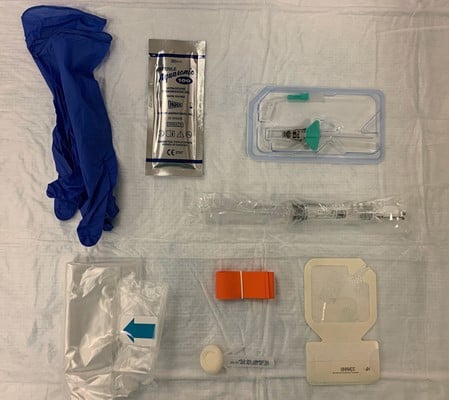

Figure 1. Supplies required for USPIV insertion. Clockwise from upper left (nonsterile gloves, sterile single-use gel, long IV catheter, saline flush, catheter dressing, tourniquet and skin prep, probe cover)

Sterility

- Large amount of practice variation but a lack of high-quality evidence.3

- ACEP recommends a single use probe cover with sterile gel while inserting USPIVs4

- ACEP does not specify whether the probe cover should be sterile

- No comment on glove use

- No studies comparing sterile to non-sterile glove use

- USPIVs inserted with non-sterile gloves have similar infection rates to PIVs inserted by landmark with non-sterile gloves4

- We recommend a probe cover and sterile gel, but do not require sterile gloves.

- Several options of probe cover exist (probe covers typically used in CVC placement, adhesive films (eg, 3M Tegaderm), wrist portion of sterile gloves4

- Tegaderm and other adhesive dressings can damage probe lenses and are not recommended by ultrasound manufacturers

- Kittisarapong in the Sept. 2019 edition of this newsletter provided an excellent overview of several new probe cover options

- Not all of these are routinely stocked in many emergency departments

- We recommend each department development a policy considering local resources

- Non-sterile ultrasound gel and equipment is a vector for infectious organisms including MRSA4

- Ultrasound equipment should be properly disinfected

- Once site is selected, non-sterile gel should be removed, and IV site cleaned

- Probes and contaminated portions of the machine should be cleaned with manufacturer-approved sanitizing wipes